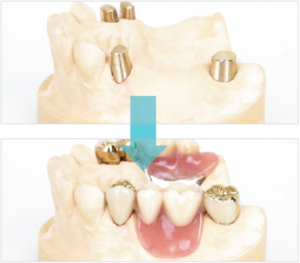

種類4~アタッチメント義歯~

アタッチメント義歯は金属クラスプ(針金)を歯と一体化にした精密義歯(入れ歯)です。一体化することによって保険の入れ歯(義歯)よりも小型にすることができます。一般的な保険の入れ歯(義歯)は金属クラスプ(針金)だけで固定します。金属クラスプ(針金)だけでは不安定なため義歯床材料(プラスチック部分)を大きくして安定するように製作されています。そのため入れ歯(義歯)装着時の際、お口の中での違和感が強くなり発音機能が悪くなり、食事がしにくくなります。アタッチメント義歯の欠点は入れ歯(義歯)を固定する時に歯を削る必要がありますが、入れ歯(義歯)と歯がしっかりと固定されるため簡単には外れにくく、装着時の違和感が少ないです。審美性(見た目の美しさ)が回復し、咀嚼機能もよく食事している時にアタッチメント義歯は外れにくく、強く噛むことが可能という利点を持つ入れ歯(義歯)です。